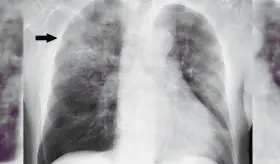

Radiólogo especialista destaca la importancia de la visión independiente del profesional en imágenes diagnósticas para detectar fibrosis pulmonar progresiva y guiar tratamientos específicos según cada patología autoinmune.

Muchas enfermedades pulmonares intersticiales pasan desapercibidas porque sus síntomas imitan a los del asma o la EPOC. Esta confusión retrasa el diagnóstico y pone en riesgo la vida del paciente.

La especialista concluye que síntomas como tos persistente, silbidos en el pecho o falta de aire que duren más de tres semanas requieren atención médica inmediata para prevenir complicaciones.